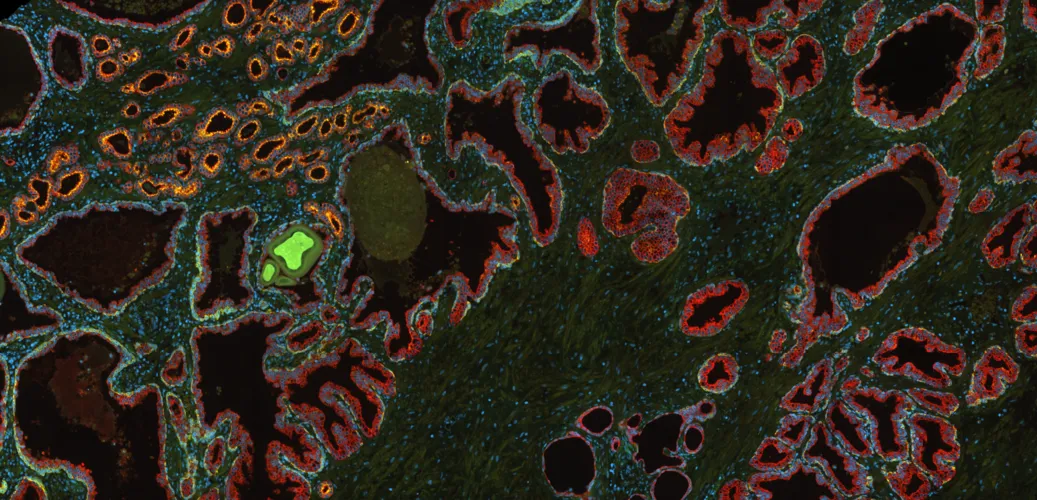

Multiplexing Techniques as Useful Tools for High-Content Phenotyping

Multiplexing enables high-content phenotyping by analyzing multiple markers in a single tissue section. Combined with TissueFAXS CHROMA and StrataQuest Apps, it delivers detailed insights into tumor microenvironments and complex cellular interactions.

What is Spatial Phenotyping?

Spatial phenotyping combines whole-slide imaging and advanced analysis to study cellular phenotypes in their native context. This approach is key in immunotherapy research, enabling insights into the tumor microenvironment and supporting informed treatment strategies.

What is Multispectral Cytometry?

Multispectral cytometry resolves spectral overlap to enable accurate, high-parameter analysis of cells and tissues. Learn how this technology, paired with spectral unmixing and advanced imaging, expands applications from cancer research to immunotherapy.